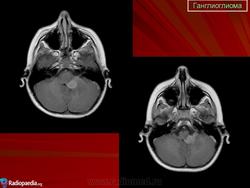

Ганглиоглиома — бифракционная опухоль, состоящая из элементов ганглиоцитомы и пилоцитарной астроцитомы. Локализуется преимущественно в полушариях головного мозга. Макроскопически представляет собой плотную четко отграниченную от ткани мозга опухоль, которая нередко содержит кисту.

Ганглиоглиома